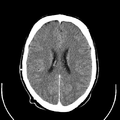

معرض الصور